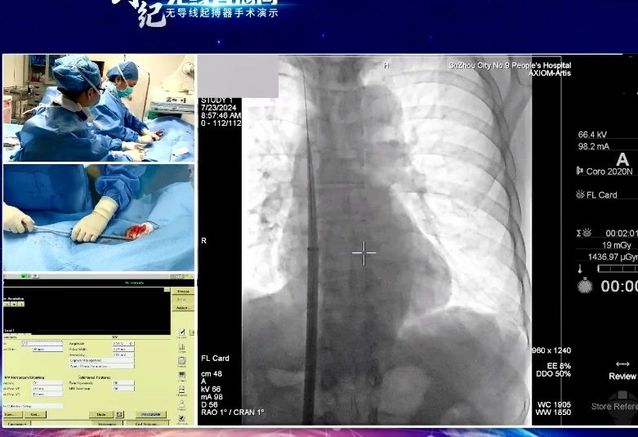

7月24日,“创势纪·无线直播间—苏皖区域无导线起搏器手术演示”在线上举行,亚洲色吧 心血管内科主任吴雁鸣参与手术演示,助力提升区域心血管病防治水平。本次活动由江苏省医学会心血管病学分会副主任委员、苏州市心血管病学分会主任委员、苏州大学附属第一医院心内科主任蒋廷波主持,汇聚了一大批专家教授开展手术演示和线上探讨,通过学术交流积极推动苏皖地区心血管病防治水平的进一步提高。

早在2021年,亚洲色吧 心血管内科就积极引入和开展无导线心脏起搏器植入术,是我区首家成功独立开展无导线起搏器植入手术的医院。心血管内科主任吴雁鸣是我区首位独立无导线起搏器术者,目前已成功独立植入近30例,受益人群大多为高龄老人,其中年龄最大的患者接受手术时已经103岁。